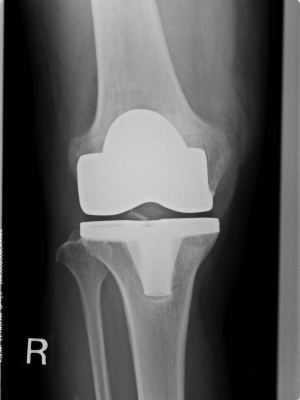

人工関節置換術

変形性関節症、関節リウマチ、その他の疾患により関節破壊を生じた疼痛のある関節に対して人工関節に置き換える手術です。疼痛が取り除かれる効果が高い手術です。

これまでは60歳以上の比較的高齢者の方の手術とされて来ましたが近年では患者さんの運動機能改善でQOL(クオリティ- オブ-ライフ)の向上が得られるなら40歳代にも適応があります。また、80歳代の患者様にも関節痛がなく元気に歩きたい方には行われます。

当院では人工関節(人工膝関節置換術、人工股関節置換術)を年間100例以上行われており、グランドゴルフや散歩など関節痛なく楽しく過ごしたくて手術を行なった80歳以上の患者様も多くいらっしゃいます。